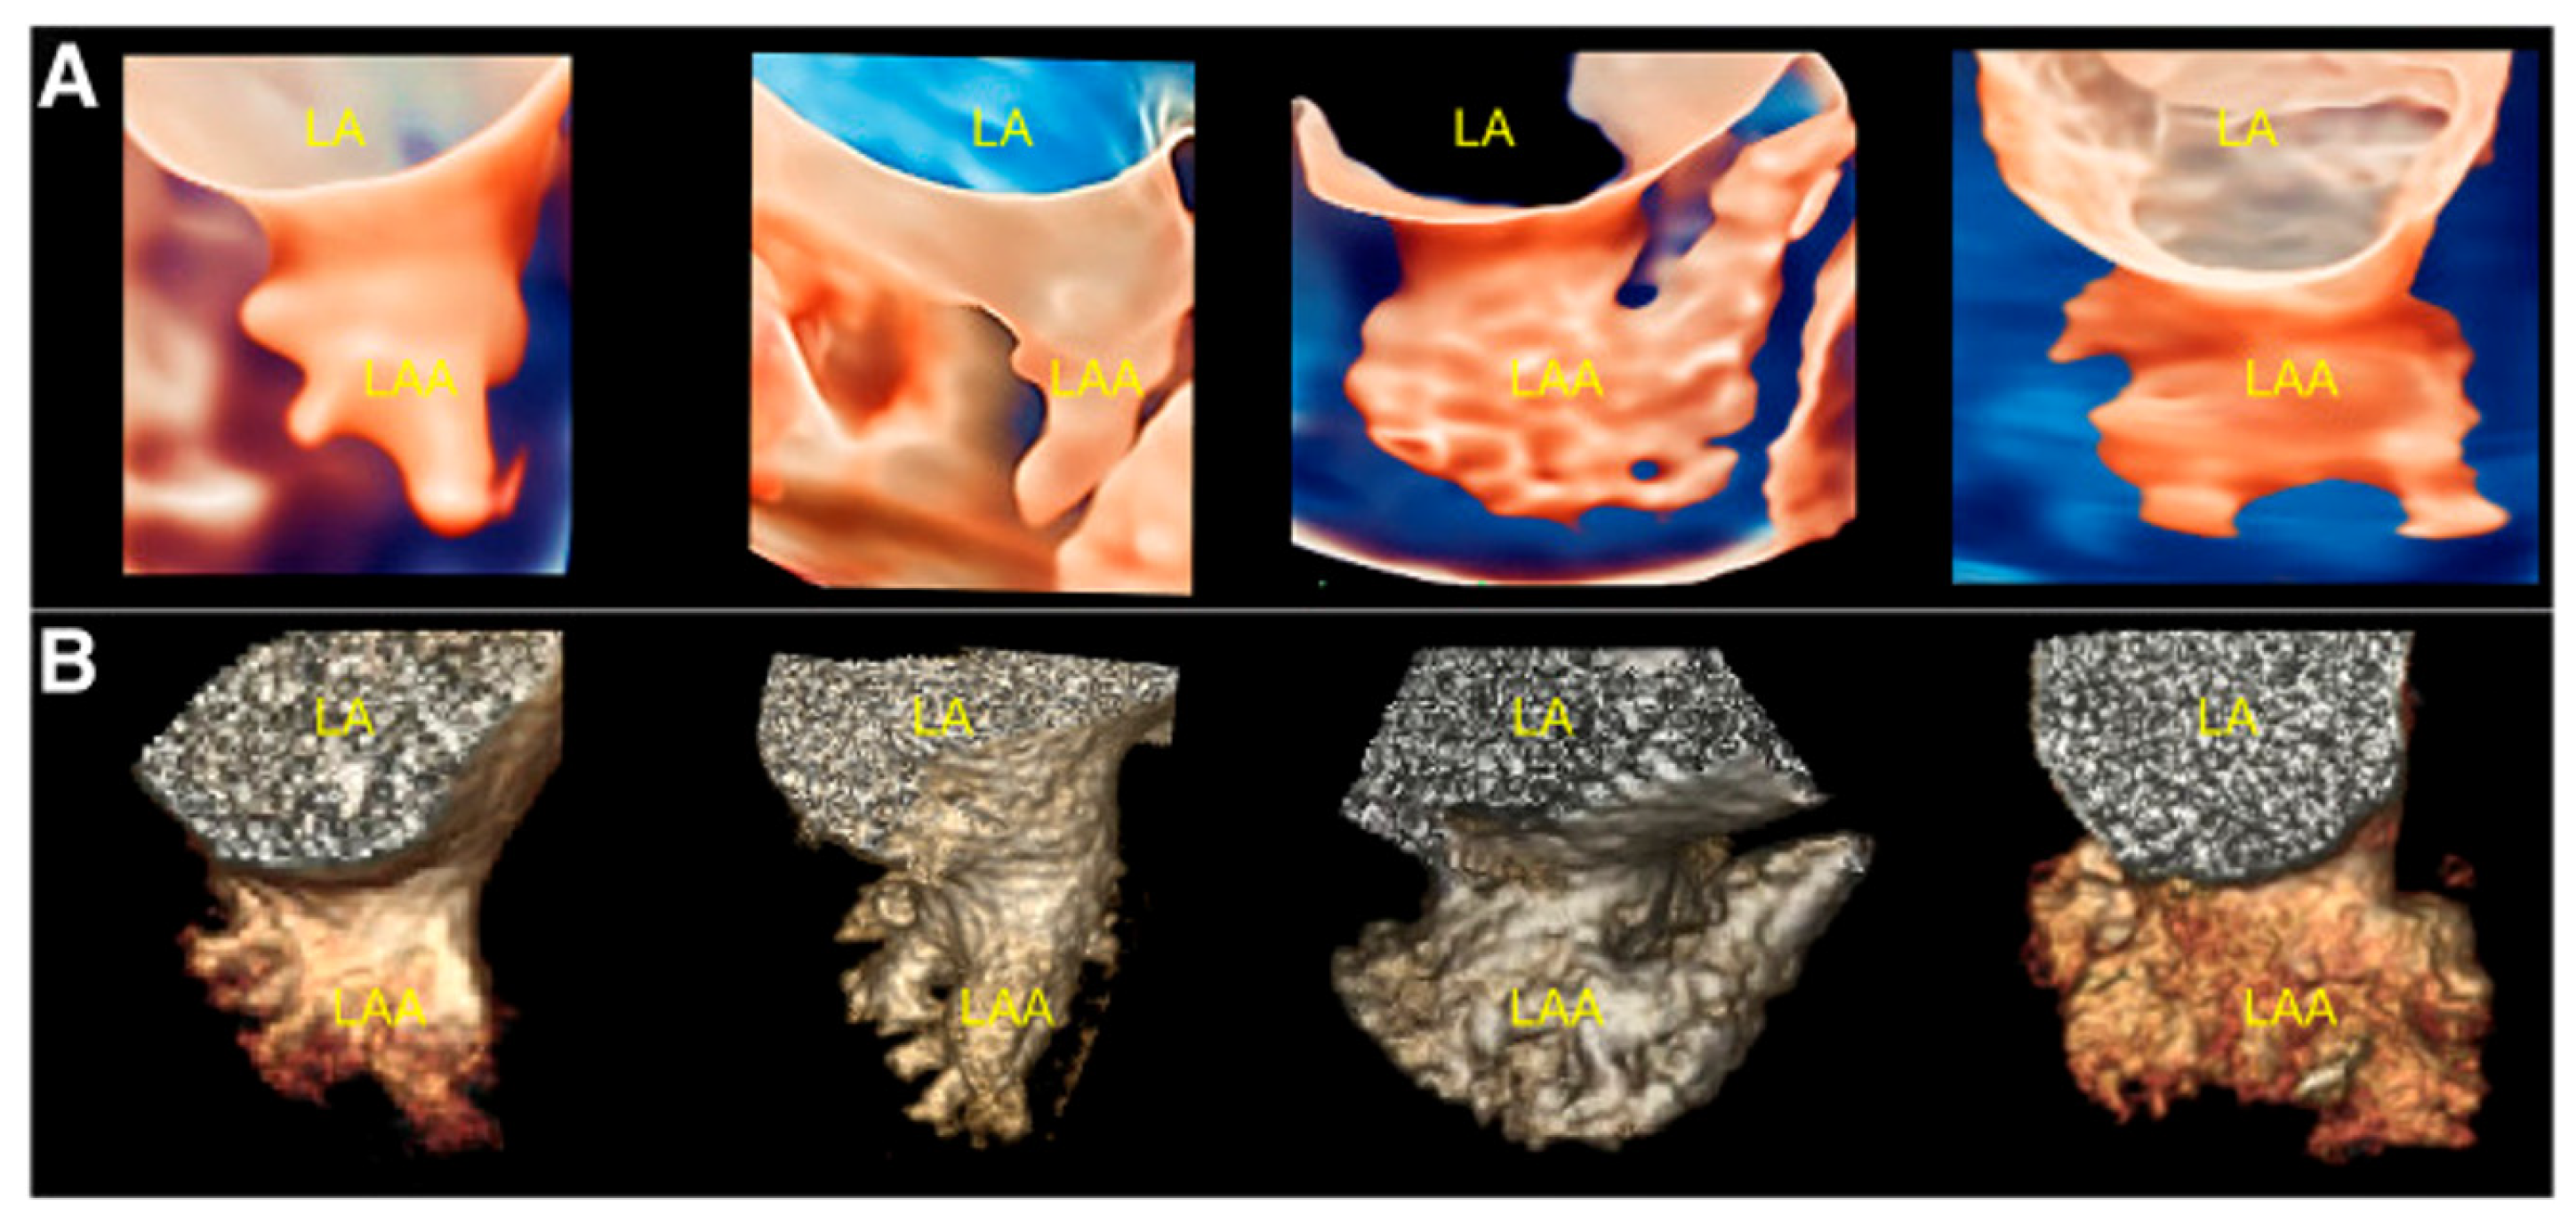

1.3. Left Atrial Appendage Anatomy and Morphology

2.2.2. LAA Measurements (Anatomy and Morphology)

2.2.3. Intra-Procedural TOE